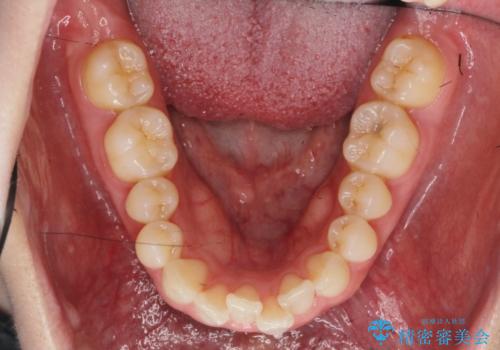

マウスピース 狭窄歯列の改善

- 噛み合わせが深い、笑った時の歯並びの改善を求めて来院されました。

マウスピース型の矯正装置インビザラインを用いた治療を計画します。

狭くなってしまった歯並びを放物線状に並べることで噛み合わせの安定・見た目の改善・ガタつきの改善を達成することができました。